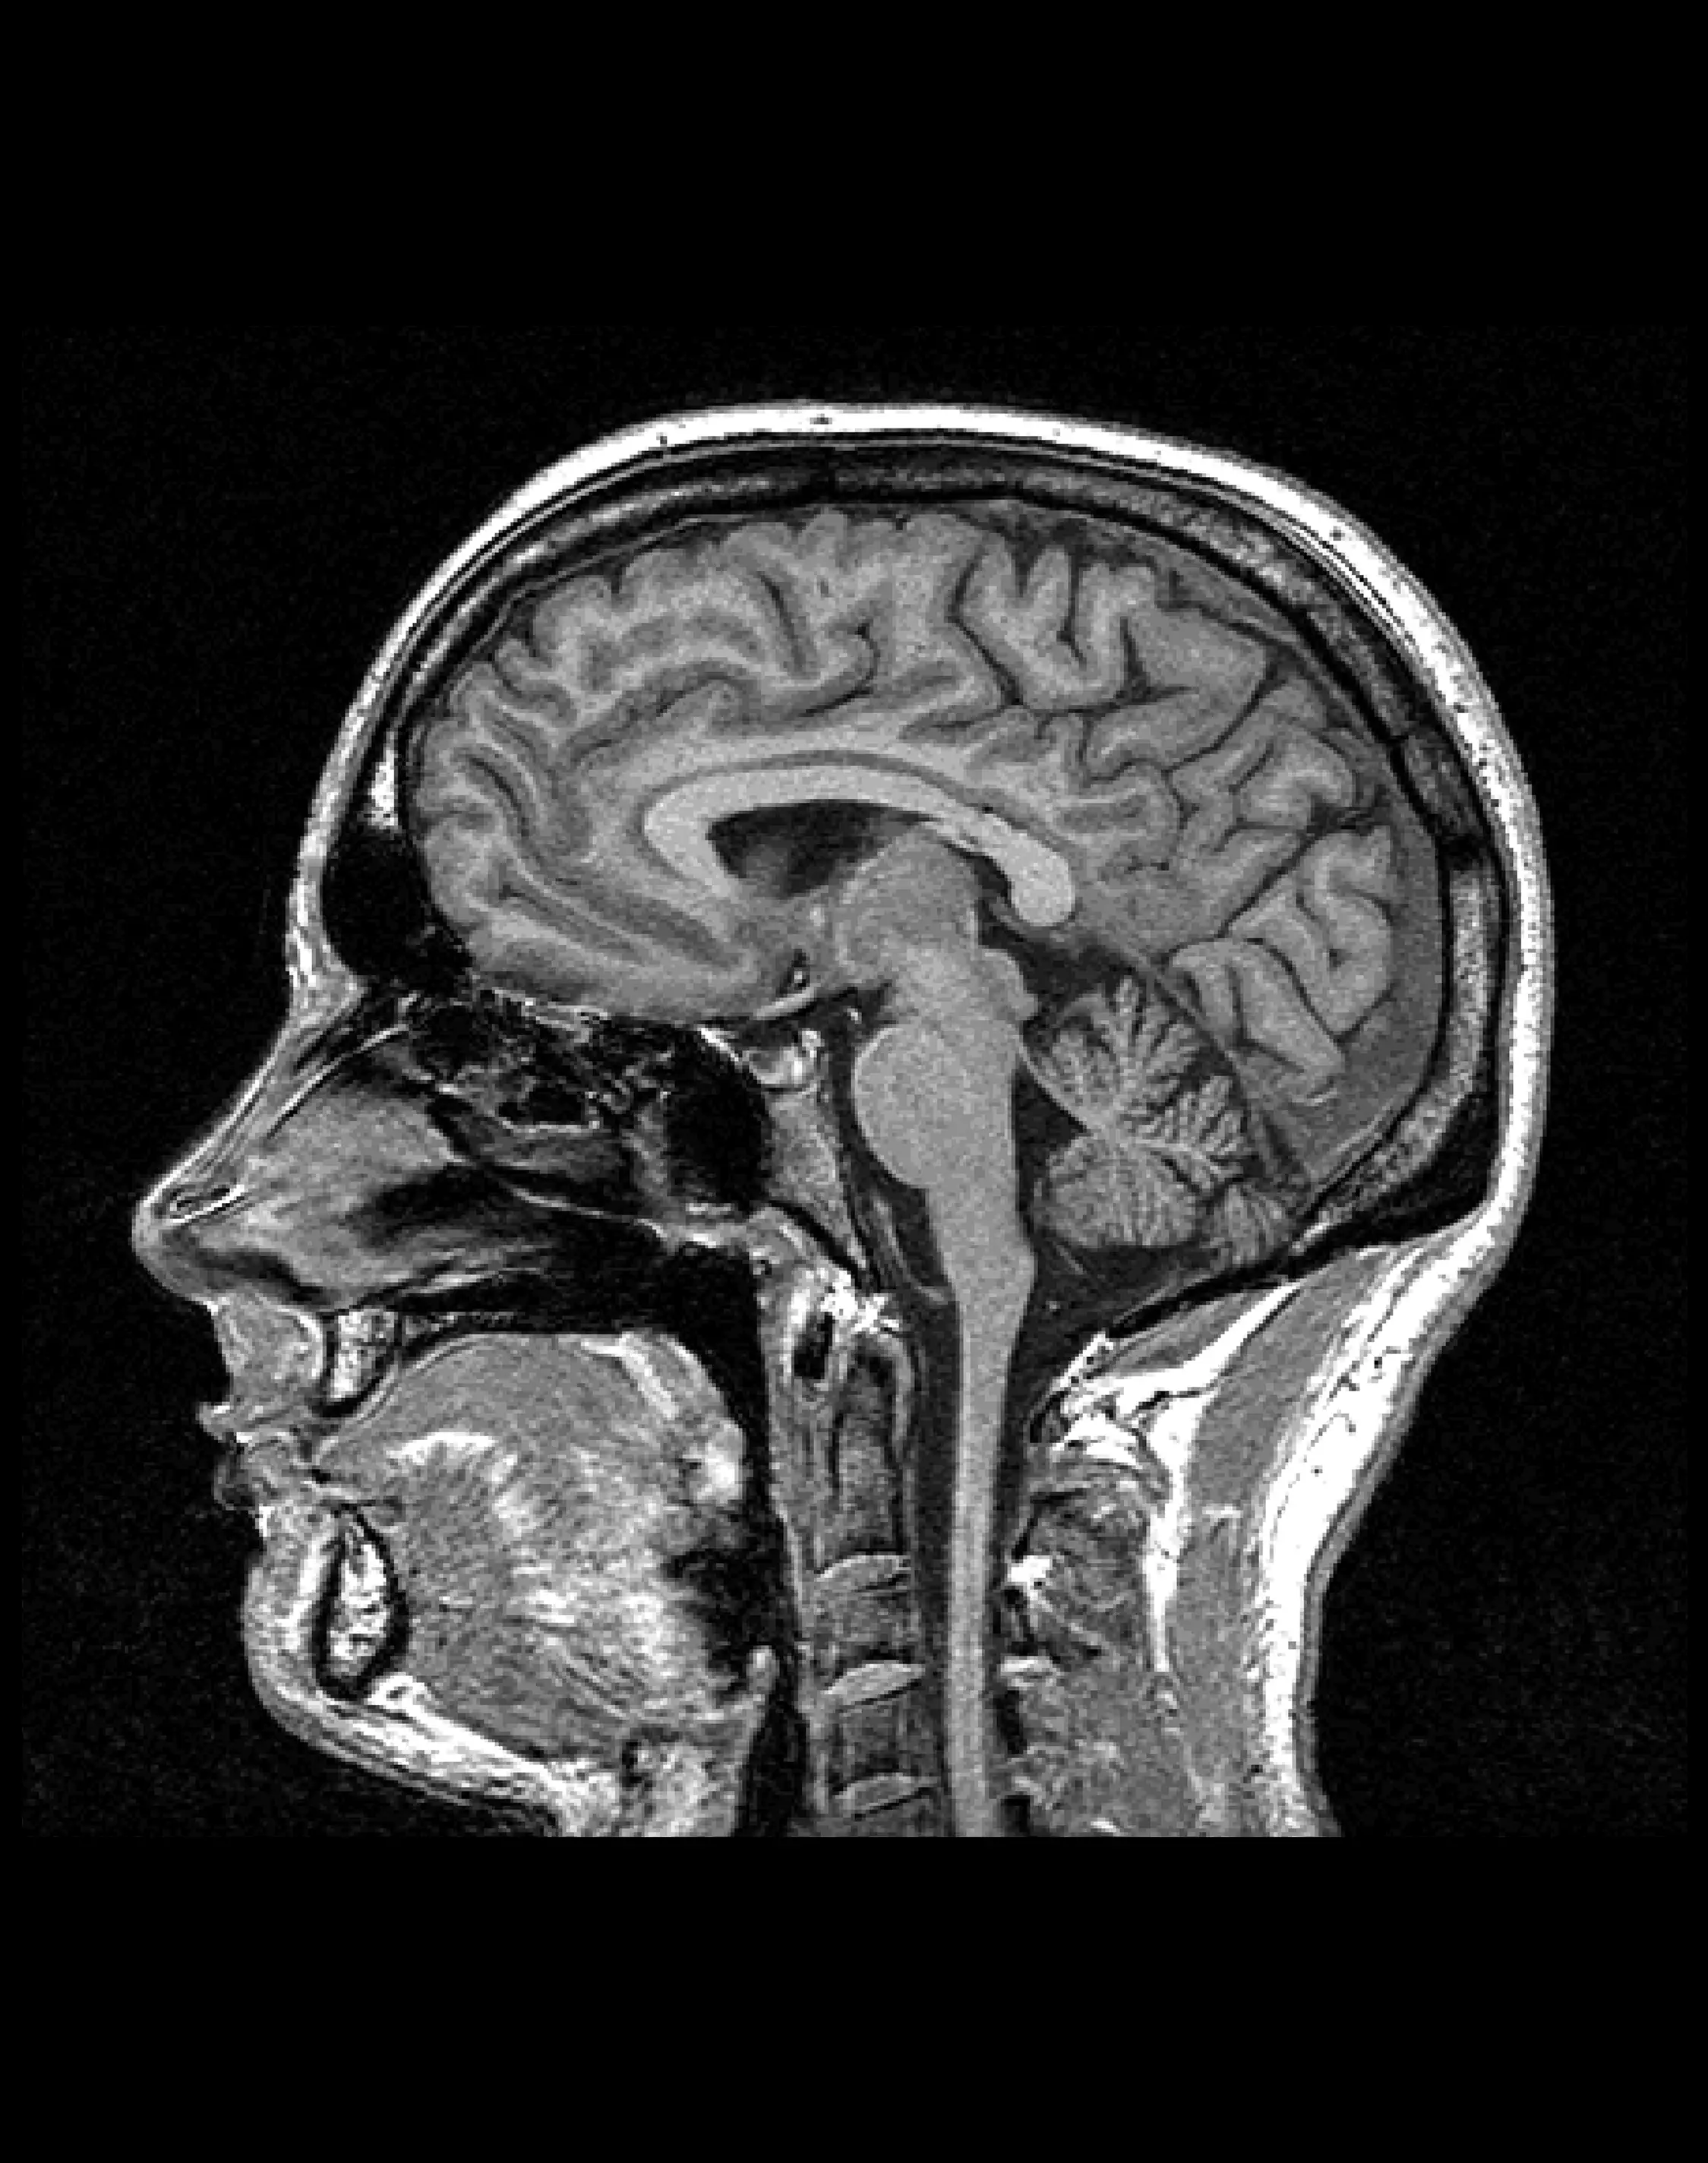

МРТ для диагностики нейроваскулярного конфликта

Диагностическая процедура, направленная на выявление патологических взаимодействий между сосудами и черепными нервами, которые могут вызывать неврологические симптомы, такие как хроническая боль или неконтролируемые мышечные сокращения.